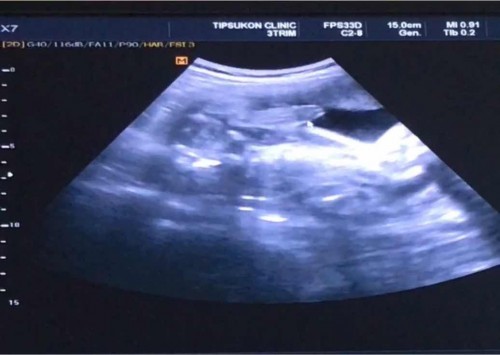

เห็นจู๋ผมมั้ยครับ

ผู้ชายชัวร์ยังครับ แม่แม่ 29 สัปดาห์ +5

เป็นเด็กเปิดเผย 😆